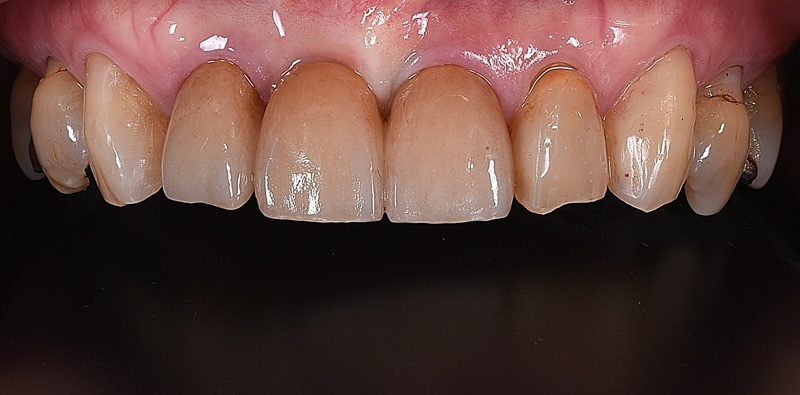

| 治療名 | 前歯のセラミックブリッジと結合組織移植術による審美修復症例 |

|---|---|

| 治療説明 |

古くなった前歯の被せ物の見た目を気にされ、ご相談いただきました。 その後、セラミックのブリッジを装着することで、天然歯のような自然な色味と形態を再現。見た目の美しさだけでなく、清掃性の高い健康的な歯ぐきを獲得することで、長期的な安定を図りました。 |

| 治療回数・期間 | 約3ヶ月 |

| 副作用とリスク | ・保険診療の銀歯に比べて費用が高額になり、治療期間も長くなることがあります。 ・結合組織移植術では、手術に伴う出血や腫れ、疼痛が生じる場合がありますが、多くは一時的です。 ・術後の腫れや違和感は数日〜1週間程度で落ち着くことが一般的です。 |

| 料金(税込) | セラミッククラウンブリッジ:396,000円 結合組織移植術:55,000円 合計:451,000円(税込) |